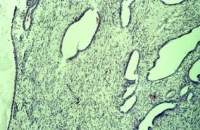

Mikroskopisch ist der Wilmstumor gekennzeichnet durch Gewebe, das verschiedenen Stufen der Nephrogenese entspricht. Es finden sich blastemische, stromale und epitheliale Zelltypen. Zum epithelialen Anteil gehören Strukturen, die tubulär oder glomerulär aufgebaut sind. Fibrozyten und myxoide Formen gehören zu den stromalen Gewebsarten. Auch glatte Muskelzellen, Knorpel-, Fett- und neurales Gewebe finden sich. Grundsätzlich ist festzuhalten, dass der Wilmstumor histologisch heterogen bzw. triphasisch aufgebaut ist. Die Anteile der Komponenten sind verschieden und korrelieren mit der Malignität des Tumors (Abbildung 2).

Tumoren des Stadium I (begrenzt auf die Niere) sind zumeist aus epithelialen Strukturen aufgebaut. Die vornehmlich aus blastomatösem Gewebe bestehenden Geschwülste gehören zu den Stadien III und IV (Stadieneinteilung s. später). Ungefähr 5% der Wilmstumoren enthalten anaplastische Nester. Die Zellen enthalten hyperchrome, große, pleomorphe (polymorphe) Kerne mit abnormalen Mitosen. Diese Tumoren sprechen im allgemeinen schlecht auf die Chemotherapie an und sind nicht komplett resezierbar (Abbildung 2).